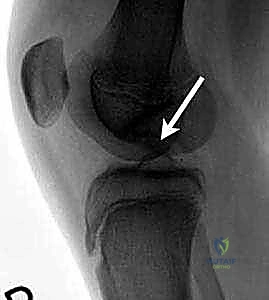

Standard radiographic evaluation includes weight-bearing anteroposterior (AP), lateral, Merchant/sunrise, and notch (tunnel) views. The notch view, taken with the knee flexed to 45 degrees, is particularly critical for visualizing the classic posterolateral aspect of the medial femoral condyle.

Magnetic Resonance Imaging (MRI) is the gold standard for assessing lesion size, depth, subchondral bone viability, and, most importantly, stability. Criteria for instability on MRI include a high T2 signal line (fluid cleft) completely surrounding the lesion, focal full-thickness cartilage defects, multiple subchondral cysts, and a high T2 signal line breaching the articular cartilage.